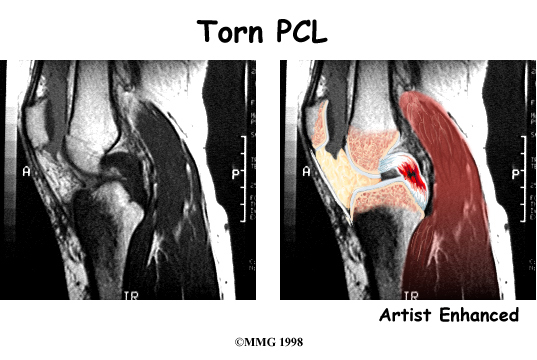

The magnetic resonance imaging (MRI) scan is probably the most accurate test without actually looking into the knee. The MRI machine uses magnetic waves rather than X-rays to show the soft tissues of the body. This machine creates pictures that look like slices of the knee. The pictures show the anatomy, and any injuries, very clearly. This test does not require any needles or special dye and is painless.

The PCL is the primary stabilizer of the knee and the main controller of how far backward the tibia moves under the femur. This motion is called posterior translation of the tibia. If the tibia moves too far back, the PCL can rupture.

Ruptured PCL